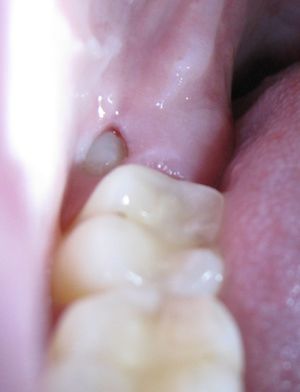

A wisdom tooth protrudes outwards from the gumline at the back of the lower teeth.